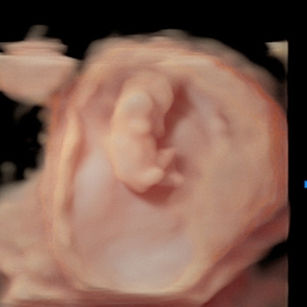

10 Weeks Pregnant

Size: ~1.2 inches (3 cm), the size of a Strawberry!

Fingers and toes separate fully.

Tail has disappeared; facial features more recognizable.